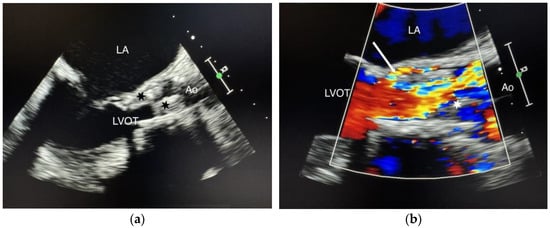

We present the case of a 75-year-old female patient, with multiple cardiovascular comorbidities, admitted to the hospital due to deterioration of her general condition. She presented with fever, asthenia, anorexia, and loss of mobility. Ten months prior to her admission, she underwent a TAVI with a self-expanding prosthetic valve (Navitor, 27 mm, Abbott Cardiovascular, Abbott Park, IL, USA). Blood cultures were positive for a multi-sensitive Enterococcus faecalis. Transesophageal echocardiography (TEE) demonstrated a 2 cm mobile mass on the aortic prosthesis leaflets, with a mean gradient of 49 mmHg and a normal left ventricle ejection fraction. Intravenous antibiotic therapy with amoxicillin-clavulanate plus ceftriaxone was initiated. One month later, TEE showed no change in the vegetation size or the mean transvalvular gradient (Figure 1a,b).

Figure 1. (a) Standard TEE showing the vegetations. Cusp enlargement and vegetations (black stars); (b) Color Doppler TEE demonstrating paravalvular regurgitation. Vegetation (white star), paravalvular regurgitation (white arrow), LA (left atrium), LVOT (left ventricular outflow tract), Ao (aorta).